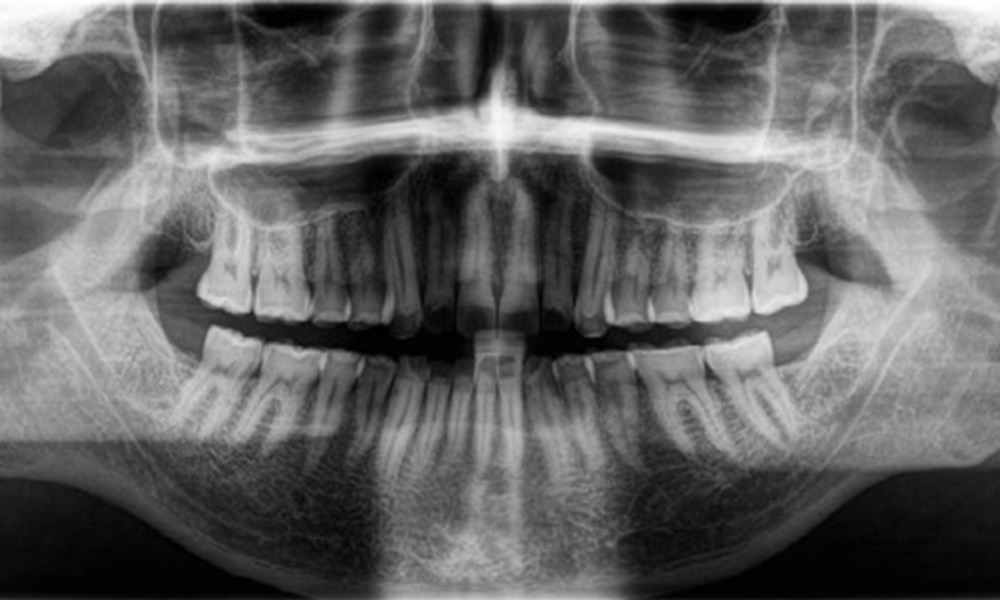

Radiological findings

Full complement of adult teeth with no caries or radiologically recognizable bone loss was observed (Fig. 6). Radiological enamel and cusp loss were particularly evident on 36 and 37.